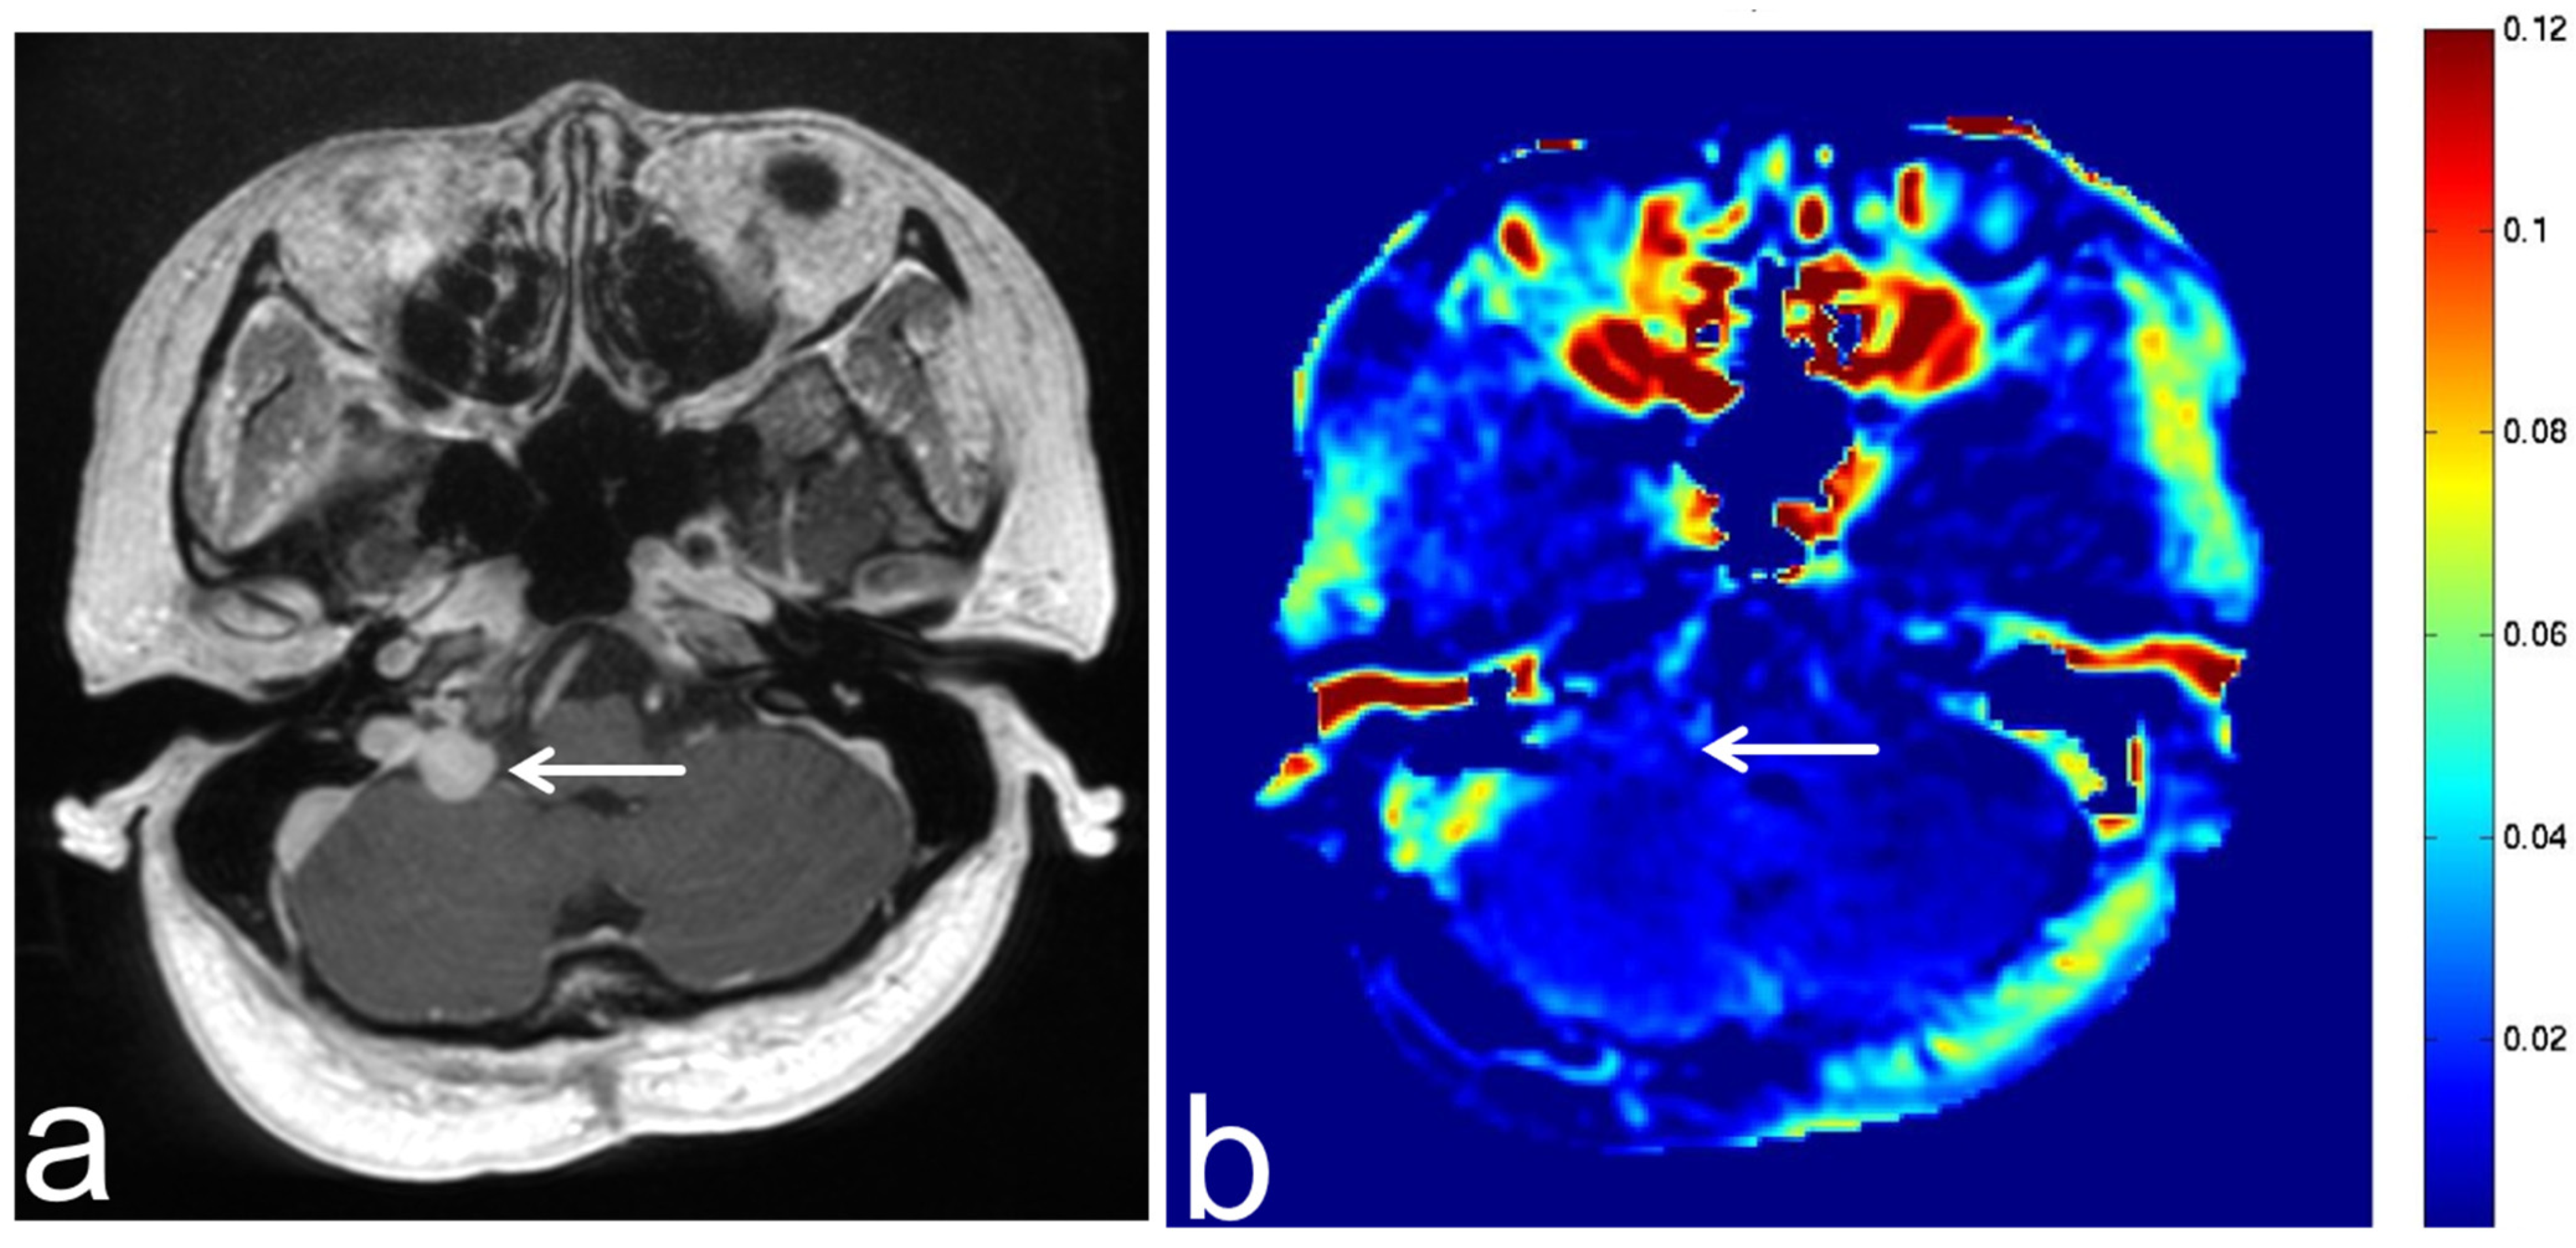

5.3. Glioblastoma

5.4. Malignant Lymphoma